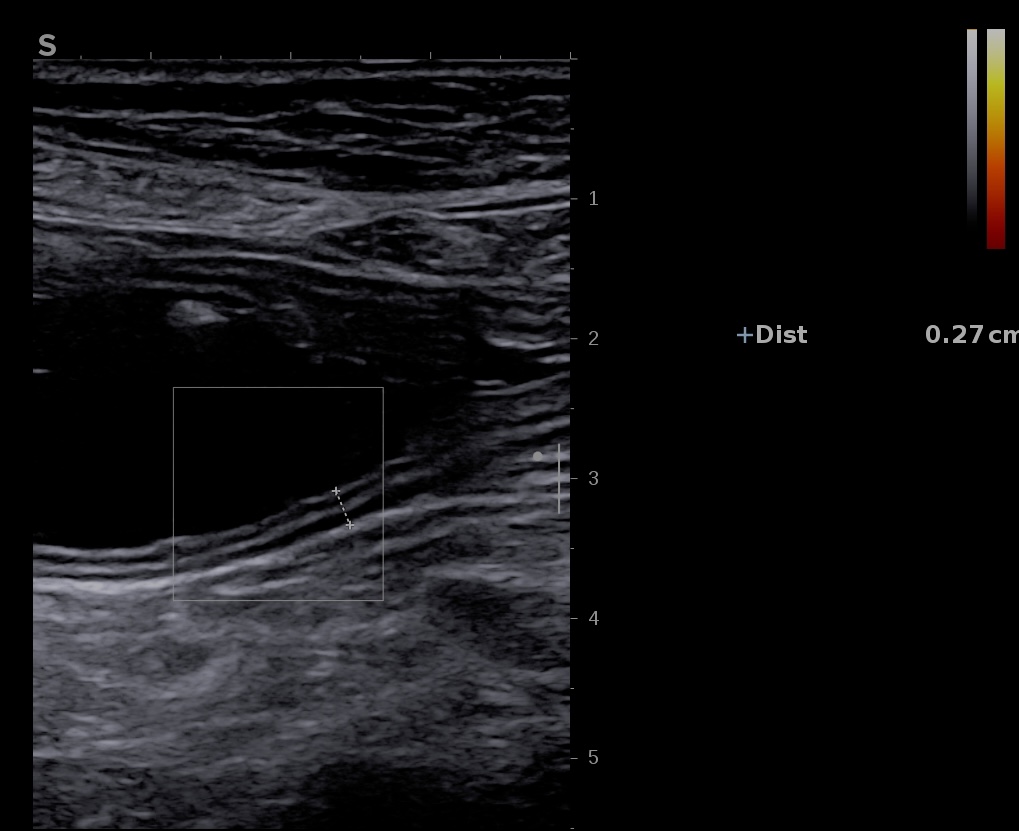

Iléon paroi 1,8 mm

Iléon terminal et appendice